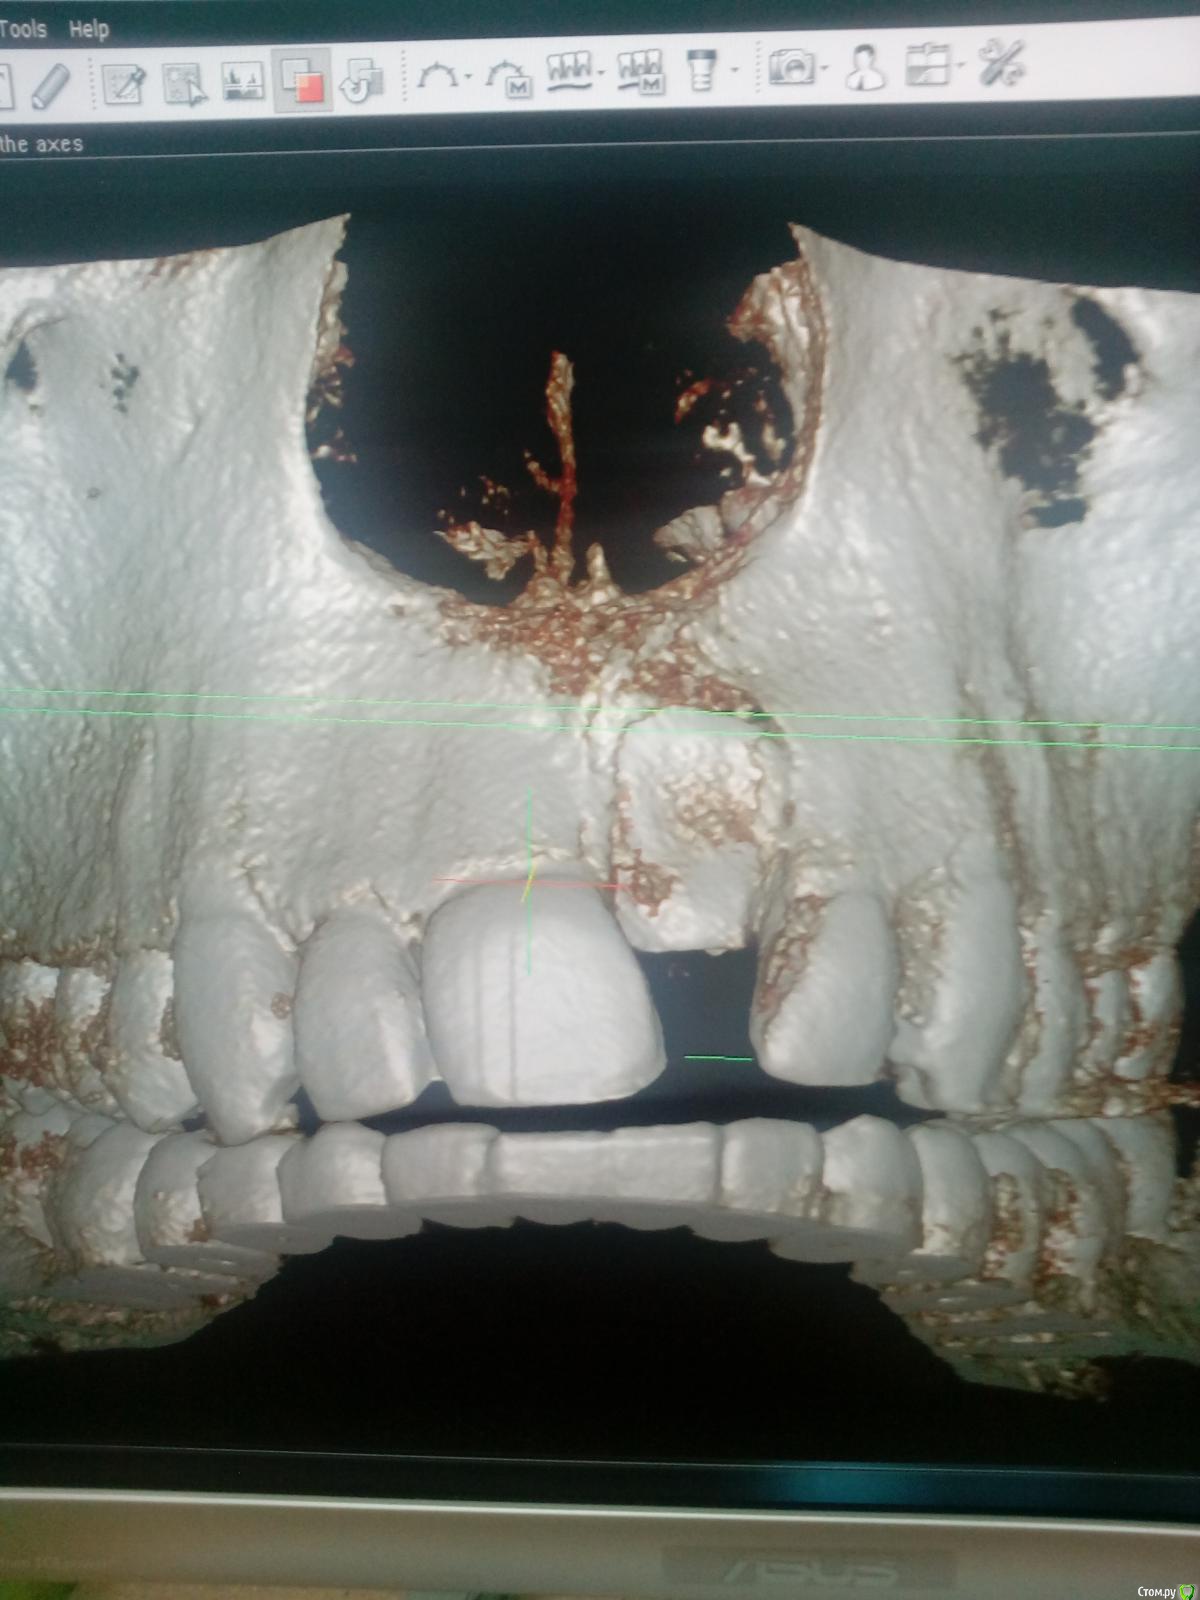

Dok22 Опубликовано 21 января, 2017 Поделиться Опубликовано 21 января, 2017 Это фотоаппарат врет, вмешательство от 4.01.2017. Родители получили инструкции+скайп ждем.Док не надо бояться начните с простого,кто если не мы? Делал так :1) Перед вмешательством седация.Анестезия.2) Вырезал лоскут с надкостницей, создав окно примерно 1кв.см.(чтоб не бороться с краями раны, я так и 8 убираю)3) Компактостеотомия ультразвуковым алмазом(кость мягкая режется легко ,им же режем сверхкомплектный зуб бывает вертится в ране можно фиксировать гладилкой)4) Сегментируем зуб,выбираем фрагменты(обязательно тщательно убрать ростковую капсулу сверкомлектного,обильно промыть водой.Аккуратно проконтролировать отсутствие ростковой зоны!!!)5) Рана не ушивается, только тампонада как при обычном удалении.6) Инструкции родителям(отеки,субфебрильная температура,болезненность это нормально не более суток,при болях детское) Вам нужен ассистент,тонкий кровоотсос,обычный слюноотсос,тонкий элеватор(3-4милиметра) и самое важное ТЕРПЕНИЕ.Спрашивайте. 1 Ссылка на комментарий

Dok22 Опубликовано 28 января, 2017 Поделиться Опубликовано 28 января, 2017 Процесс пошол. Ссылка на комментарий